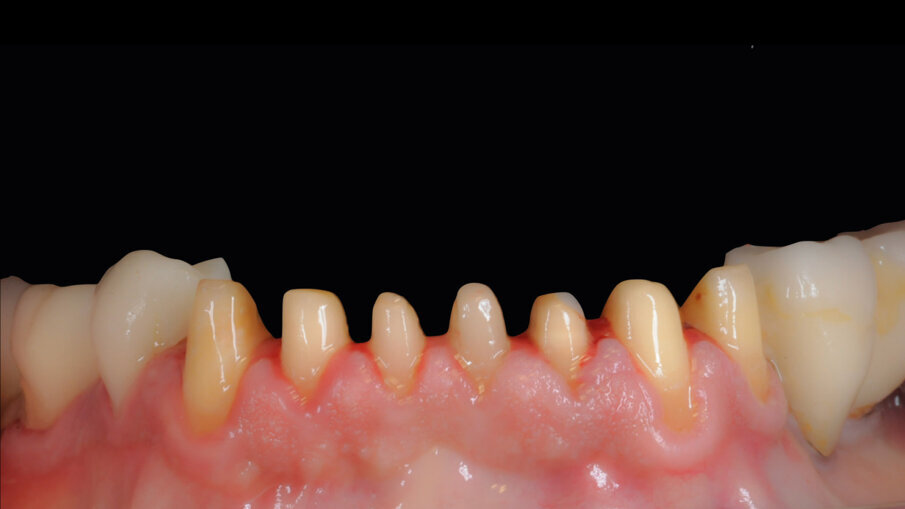

Il paziente lamentava l’aspetto estetico e la riduzione della capacità masticatoria, sottolineando l’impossibilità di affrontare molteplici visite di riabilitazione protesica (Fig. 1). Si è proceduto con una seduta di igiene orale approfondita, esami radiografici endorali e una scansione intraorale per registrare in dettaglio lo stato iniziale del paziente. Successivamente, sono state rimosse le lesioni cariose dagli elementi affetti, gravemente compromessi ma recuperabili (Fig. 2). È stato proposto al paziente un trattamento chairside in grado di risolvere i problemi funzionali ed estetici in poche ore, utilizzando preparazioni minimamente invasive e la tecnica di stampa dei restauri eseguita direttamente in studio. Dopo l’accettazione del paziente, sono state effettuate preparazioni mini-invasive, levigate e lucidate con strumenti abrasivi siliconici a grana decrescente (media/fine). Ultimate le preparazioni e verificate le condizioni dei tessuti molli e la visibilità dei margini cervicali, si è proceduto con la scansione intraorale delle arcate e la registrazione dei rapporti occlusali (Fig. 3).

Figg. 2, 3_Preparazione gruppo frontale da 33 a 43.